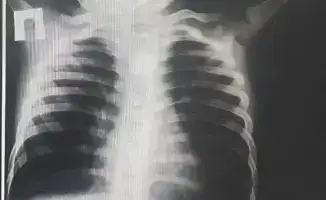

В Туркестанской областной детской больнице была проведена сложная операция на ребенке, у которого застряла батарейка в пищеводе. Мать пациента сообщила, что после еды у него начался сильный кашель, рвота и обильное слюноотделение. При рентгеновском обследовании в районной больнице был выявлен металлический предмет круглой формы, который находился в верхней части пищевода.

Ребенка немедленно доставили в Туркестанскую областную детскую больницу на скорой помощи. В приемном отделении хирурги и эндоскописты провели осмотр и дополнительные исследования, которые подтвердили наличие инородного тела. В связи с угрозой для жизни ребенка, врачи приняли решение о проведении операции.